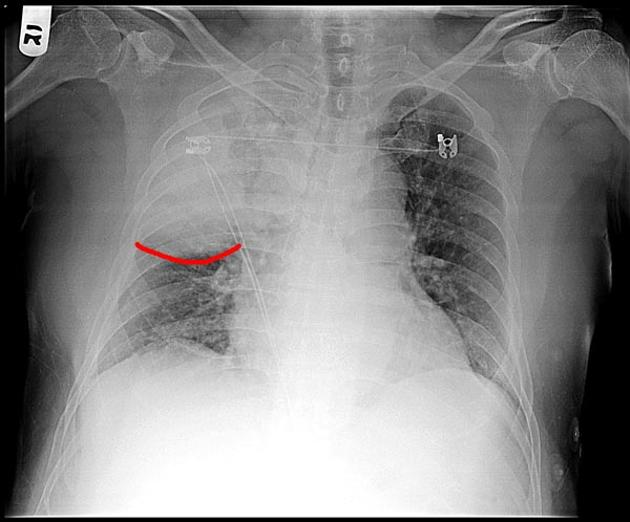

78 一位 68 歲男性,長期酗酒,因發燒、咳嗽併咖啡色濃痰、呼吸困難,胸部 X 光顯示右上肺野白色堅

實性變化(consolidation)合併肺葉間隙鼓漲(bulging interlobar fissure),此病患肺部感染的菌種最

可能為何?

The bulging fissure sign refers to lobar consolidation where the affected portion of the lung is expanded, causing displacement of the adjacent fissure. Any type of pneumonia or space-occupying process can lead to bulging (sagging) fissure sign.

Classically, it has been described in right upper lobe (RUL) consolidation secondary to Klebsiella pneumonia. It is now rarely seen due to prompt antibiotic therapy for suspected pneumonia.